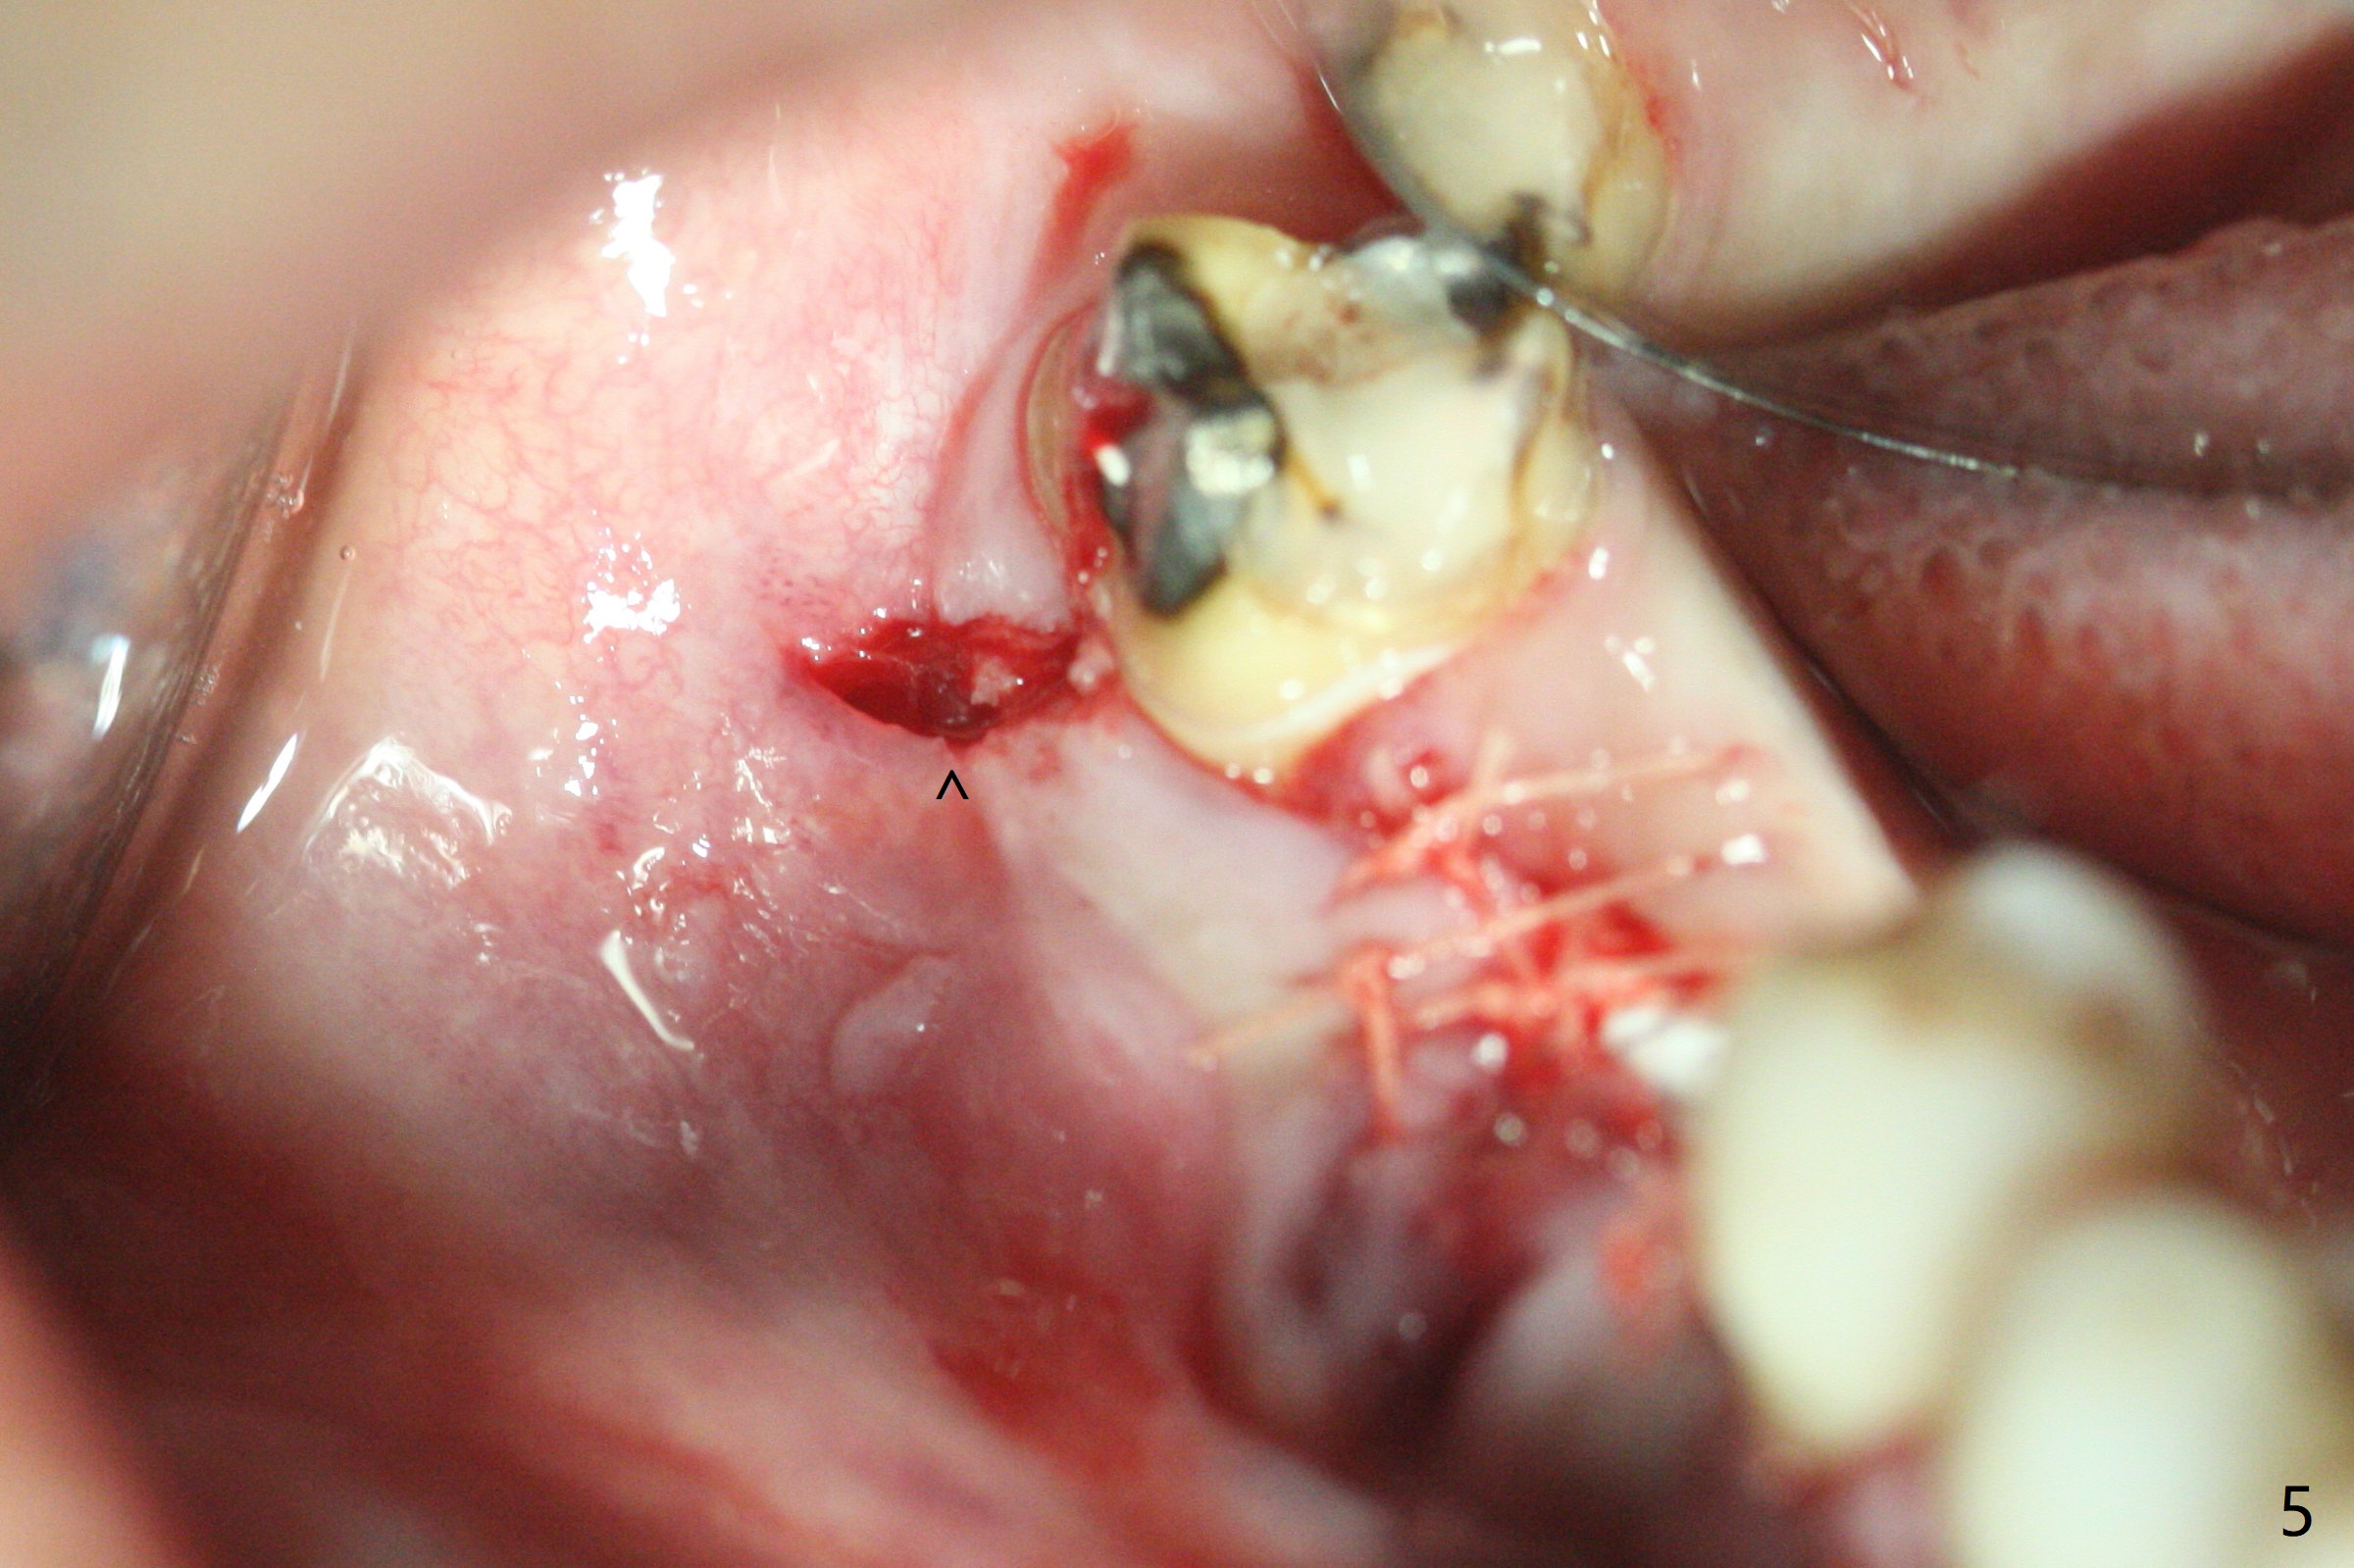

In spite of use of water pik, the coronal threads of the implant at #30 remain exposed 2 months postop (Fig.1). Envelop incision with mesial and distal accessory release ones reveals buccal bony defect (Fig.2). After 2nd spin (1500 RPM for 10 minutes), PRF forms in the red tube (Fig.3 yellow gel-like). Following use of Titanium brush, sticky bone is place (not so bone block-like, Fig.4), followed by a large piece of PRF membrane (from the red tube of Fig.3), Cytoplast (Fig.5,6 white porous) and a small piece of PRF membrane (from the white tube, next to the thin gingiva). The distal (Fig.6 D) and mesial (Fig.7 M) flaps are approximated (arrows without suture) as much as possible as well as lingual. 4-0 Polyglycolic Acid suture is used. Periodontal dressing dislodges 5 days postop. When the patient returns 1 week postop, he is pain free. Although Cytoplast is exposed, the surrounding gingiva seems to be healthy (Fig.8). Later the permanent crown of #31 is temporarily cemented with OHI. It appears that Cytoplast could be used to cover PRF membranes for soft tissue defect, followed by immediate provisional at the stage of immediate implant. The discolored (apparently contaminated) Cytoplast seems to be expelled 6 weeks postop (Fig.9). When the latter is removed, the soft tissue looks normal (Fig.10). Two weeks later, the apparently normal, but thin gingiva forms over the former granulation tissue (Fig.11 *, as compared to Fig.10). There is not enough bone coronal to the implant plateau 2 months post graft (Fig.12). Three months later, bone graft will be re-placed possibly with uncover.